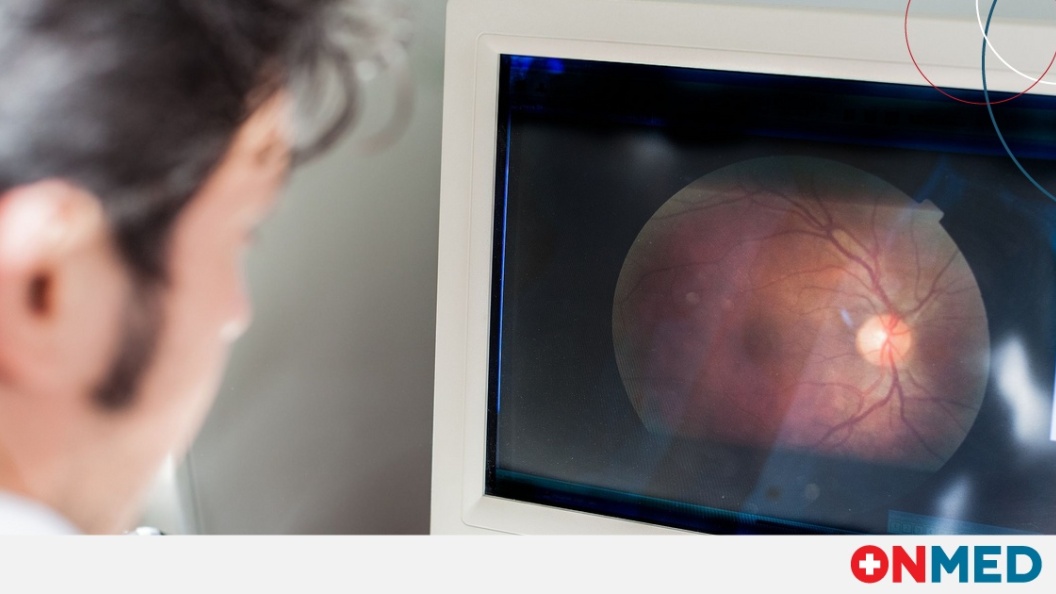

Οφθαλμολογική απεικόνιση μπορεί να αποκαλύψει κίνδυνο για την καρδιακή υγεία

Μια νέα μελέτη διαπίστωσε ότι μια απλή οφθαλμολογική σάρωση μπορεί να βοηθήσει στην πρόβλεψη των κινδύνων για την καρδιακή υγεία, προσφέροντας έναν πιθανό μη...